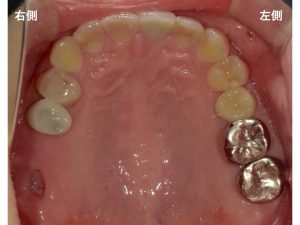

以下は初診時です。

上顎を噛む面から写真撮影した状態です。

左側の奥から2歯に金属製の被せ物が装着されていました。